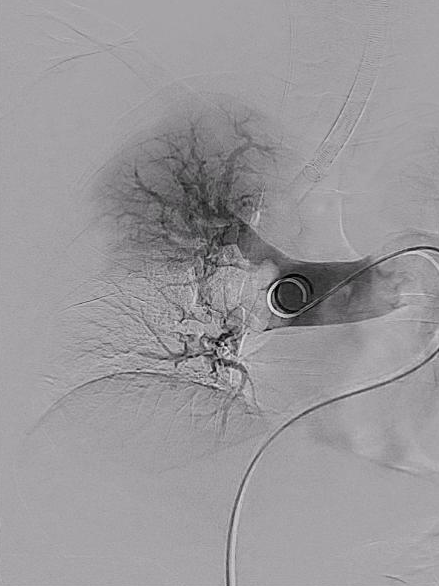

血管外科团队顺利完成股静脉穿刺,置管造影,然后在DSA指引下顺利送入抽吸导管至左右肺动脉主干,以取栓系统取出大量新鲜、陈旧混杂血栓,双肺末梢动脉即刻恢复灌注。

左肺取栓前后影像

术后评估:

患者术后麻醉清醒,呼吸平稳顺畅,右心缩小,BNP、肺动脉压力下降,临床症状、指标得到明显改善。

本次手术为该器械首次临床运用。此例手术证明该取栓系统各方面优点:术前准备时间短,术中血栓清除效率高,术后无需辅助溶栓治疗,术后恢复快。